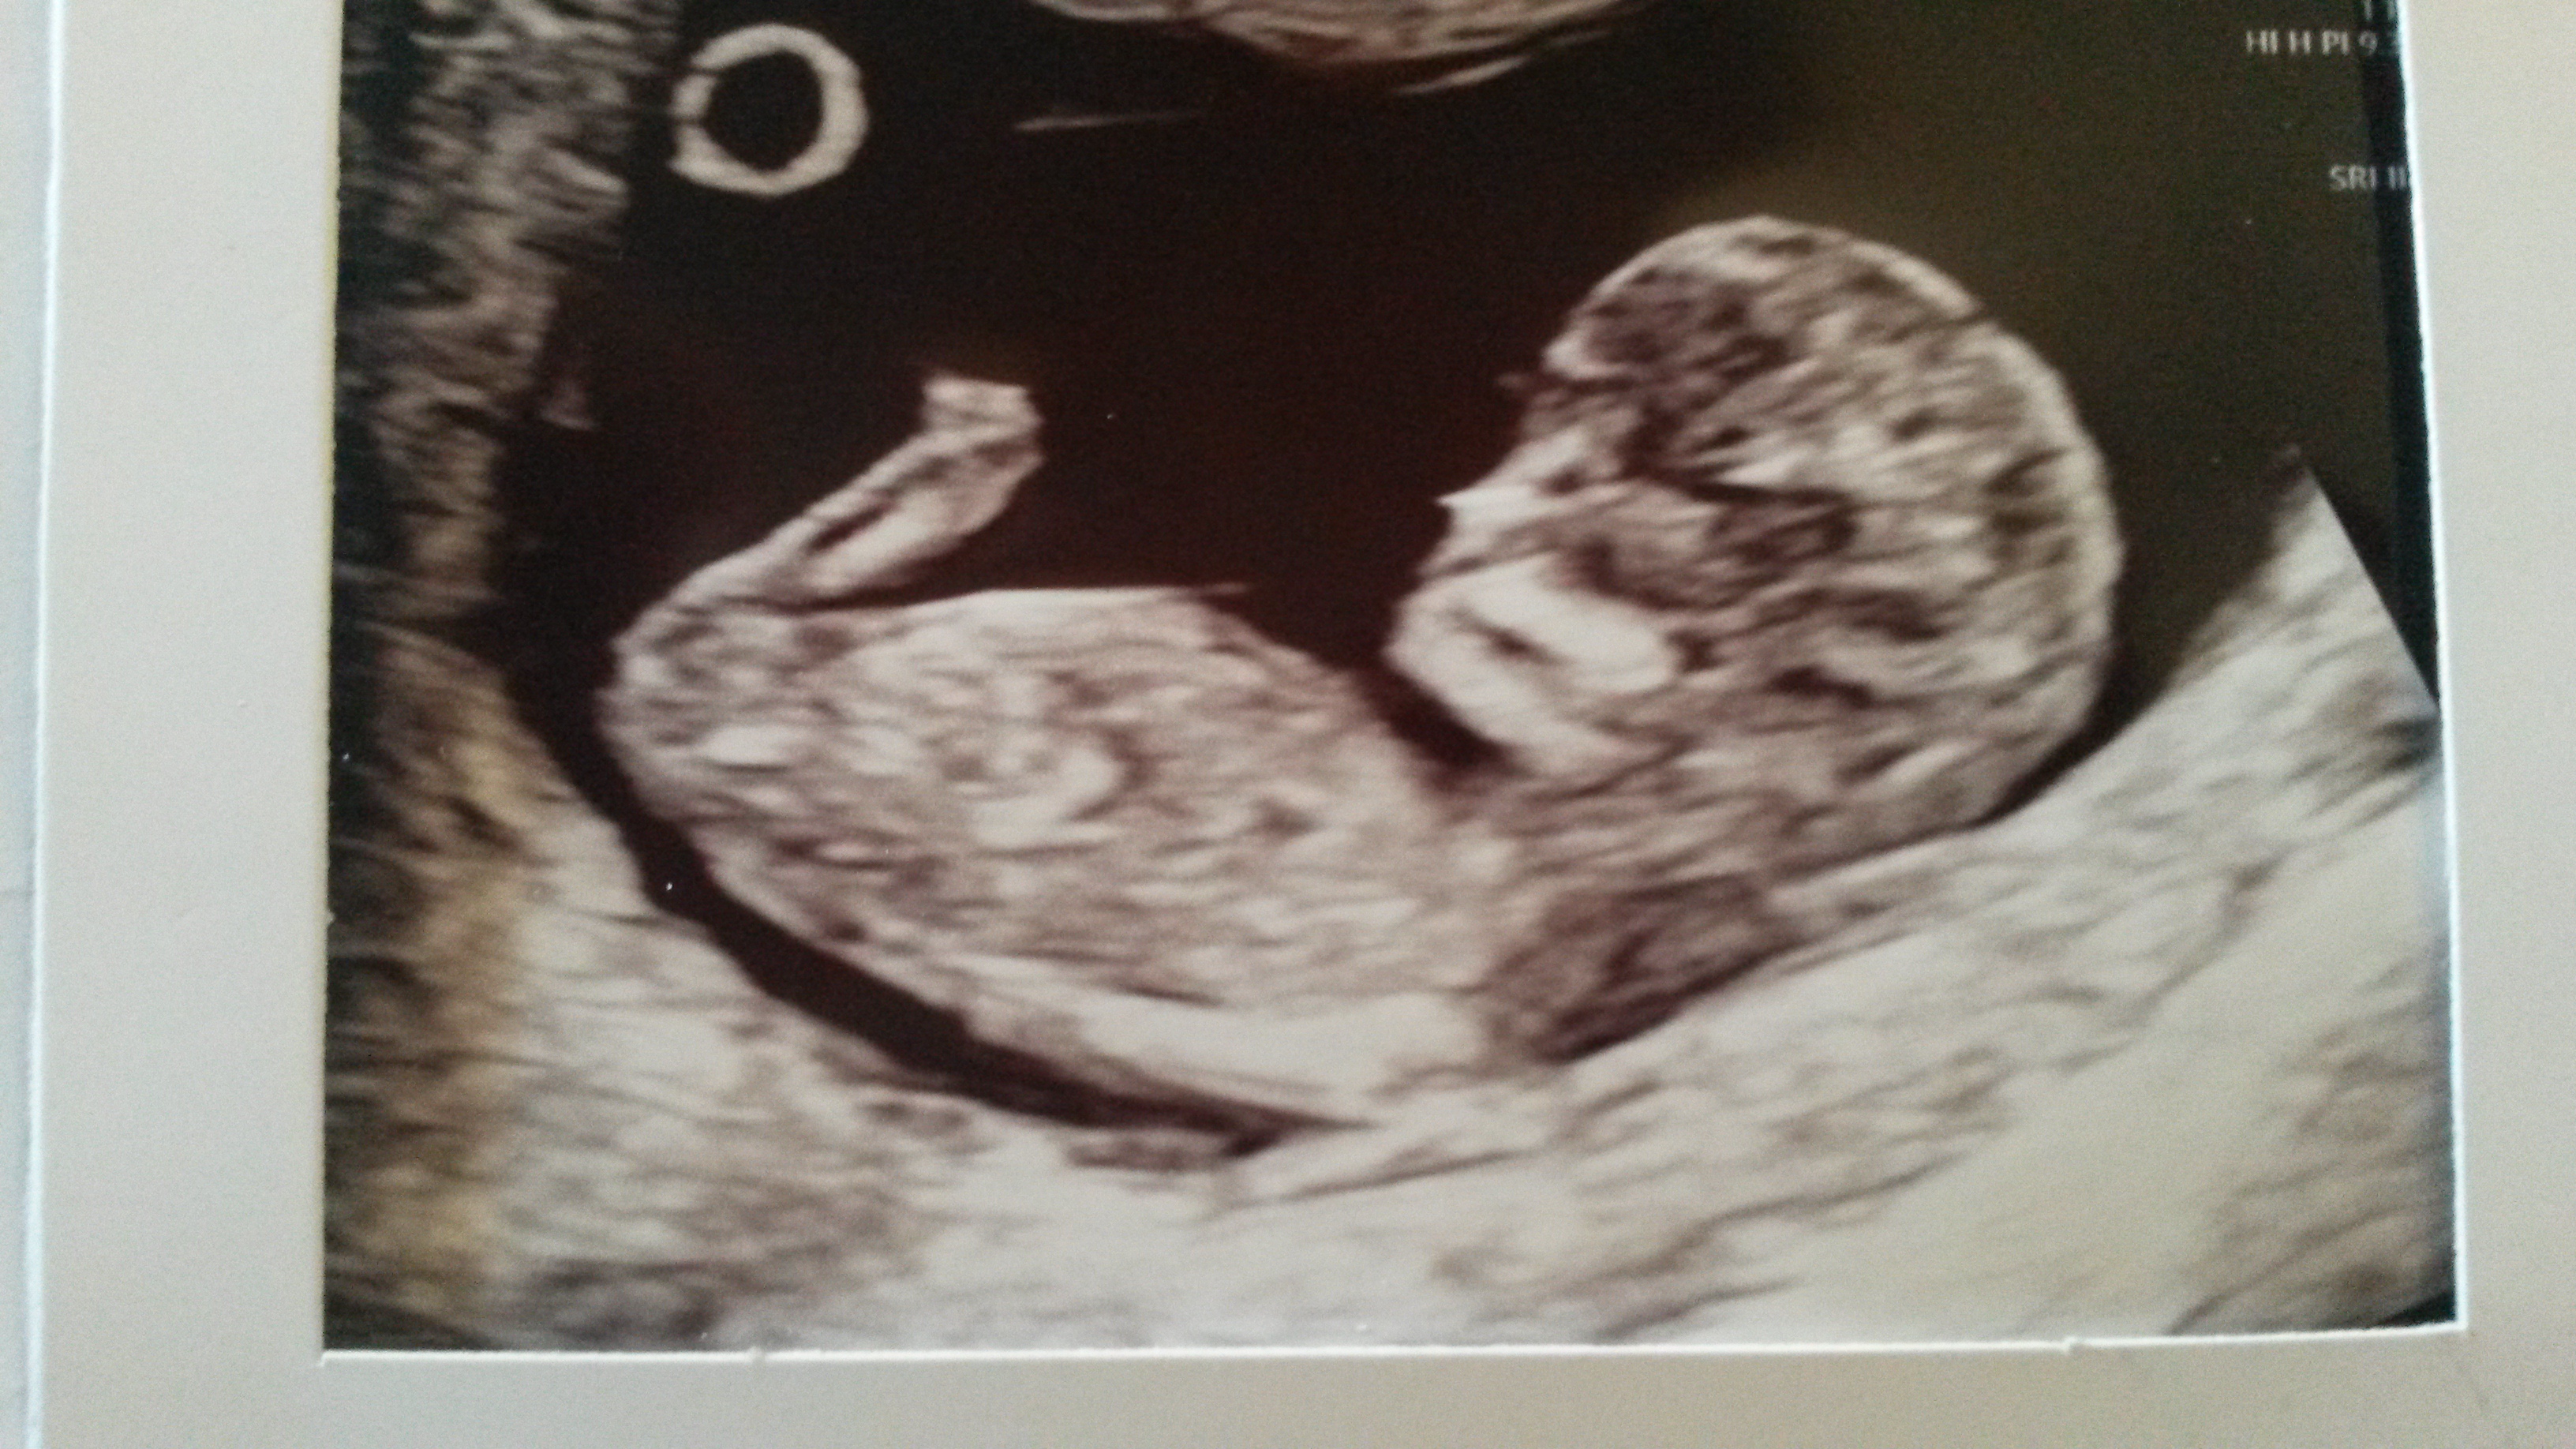

So no nub. Can I get anything off skull theory or is it still early?Attachment 41213dAttachment 41214

It's too early for me, but beautiful baby.

I’m bad with skull theory